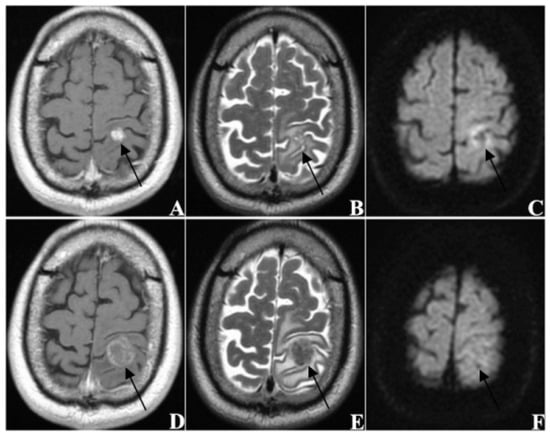

| enhanced pattern | |

| homogeneous | 113 (35.0) |

| heterogeneous | 105 (32.5) |

| ring-like | 105 (32.5) |

| EI | 2.928 × 10−22 |

| EI > 3.835 | 2 | −2.007 | 2.928 × 10−22 |